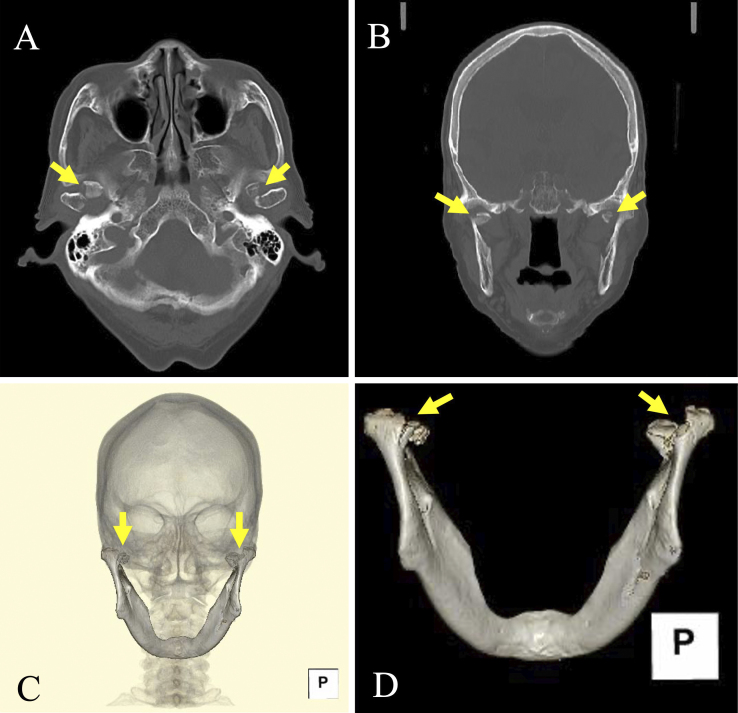

Bilateral Mandibular Condylar Fractures.

双侧下颌髁骨折。